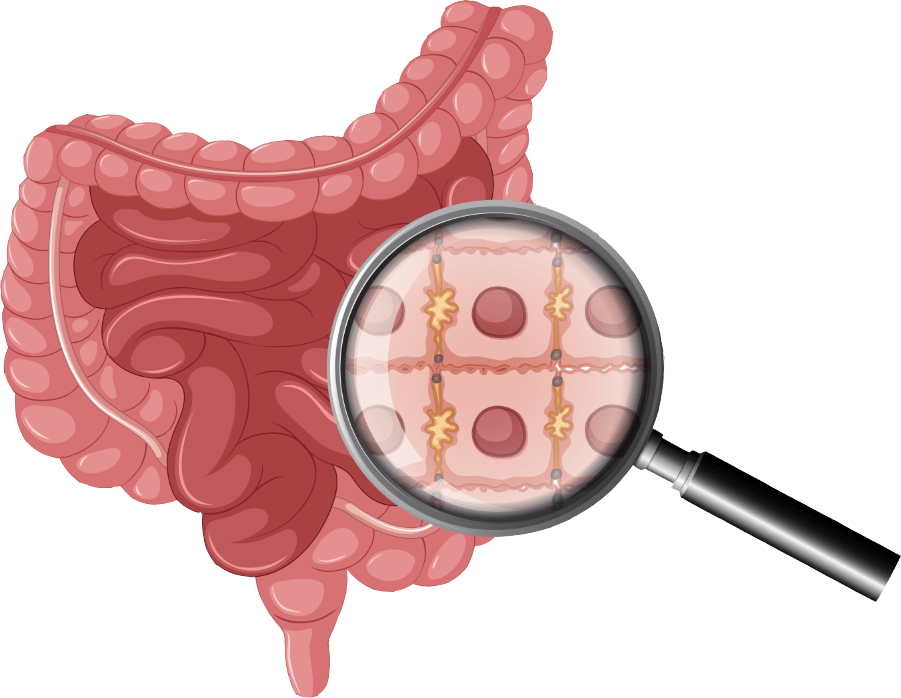

المركز التخصصي لعلاج القولون